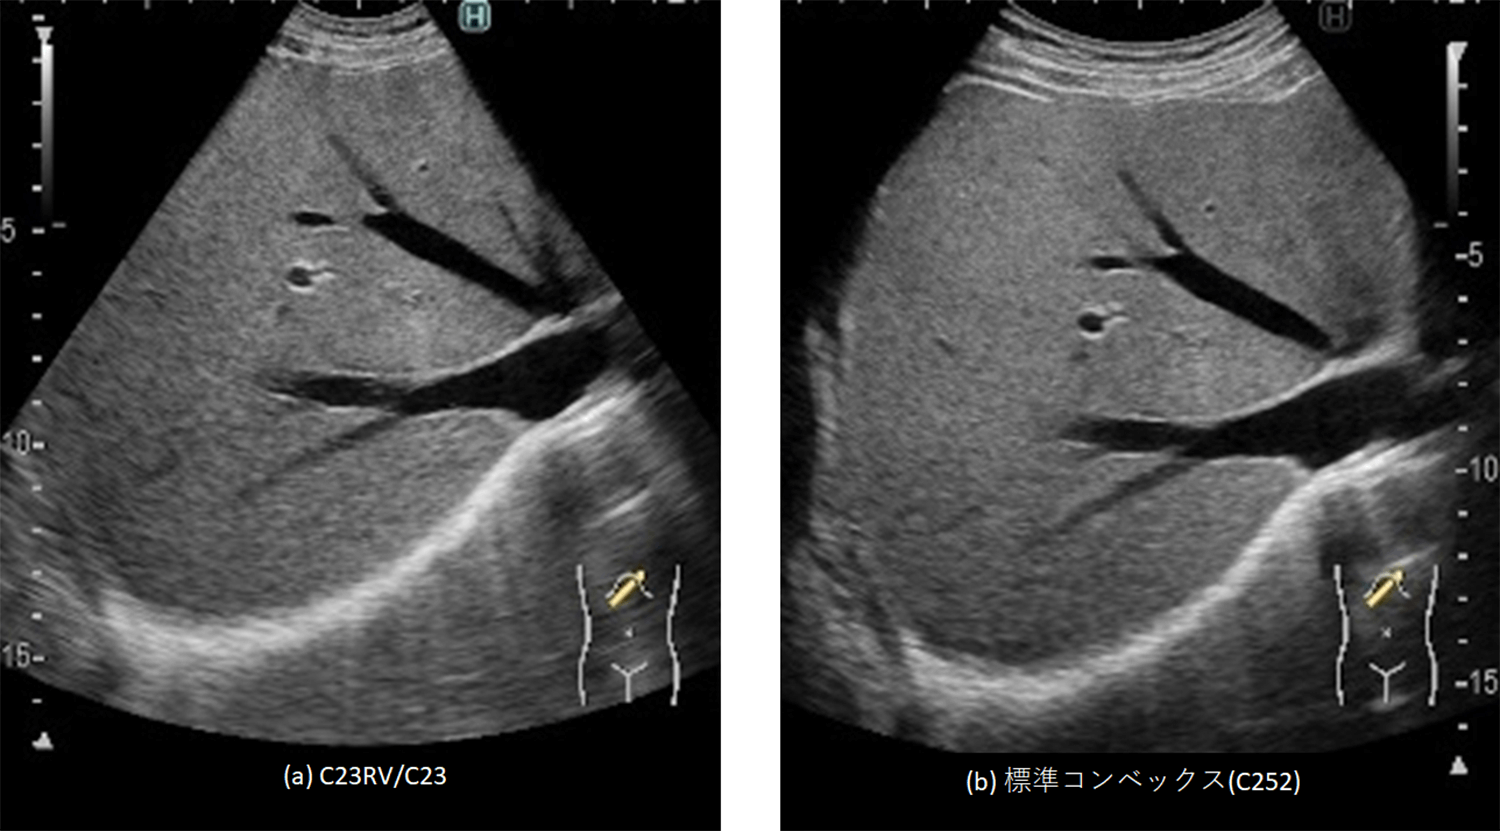

マイクロコンベックスプローブは標準コンベックスプローブと比較して音響放射面積が3分の1程度と小さく、一般的に深部の感度、空間分解能が劣る。深部の感度と空間分解能は音響放射面積、音響エネルギーに依存するが、マイクロコンベックスプローブでは小型の形状を維持するため、音響放射面積には制限がある。また、音響エネルギーも音響放射面の発熱制限により、出力が制限される。今回、圧電単結晶の採用による広帯域化と放熱構造の見直しによる音響エネルギーの向上を図ることで、深部の感度と空間分解能を改善した(図1)。

図1 C23RV/C23と標準コンベックスのUS画像